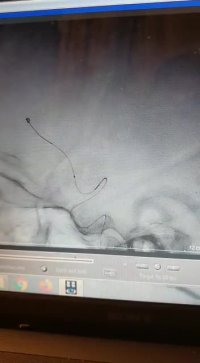

درمان آنوریسم مغزی به روش استنت و کویل گذاری

دکتر رادنوش پشم فروش فوق تخصص اینترونشنال و نورورادیولوژی

جراحی بسته آنوریسم مغزی توسط کویل و استنت

کویل گذاری داخل آنوریسم مغزی

کویل گذاری آنوریسم بزرگ داخل مغزی

گذاشتن استنت فلودایورتور یا استنت داخل مغزی جهت درمان آنوریسم مغزی

کویل گذاری آنوریسم بزرگ شریان کاروتید داخلی